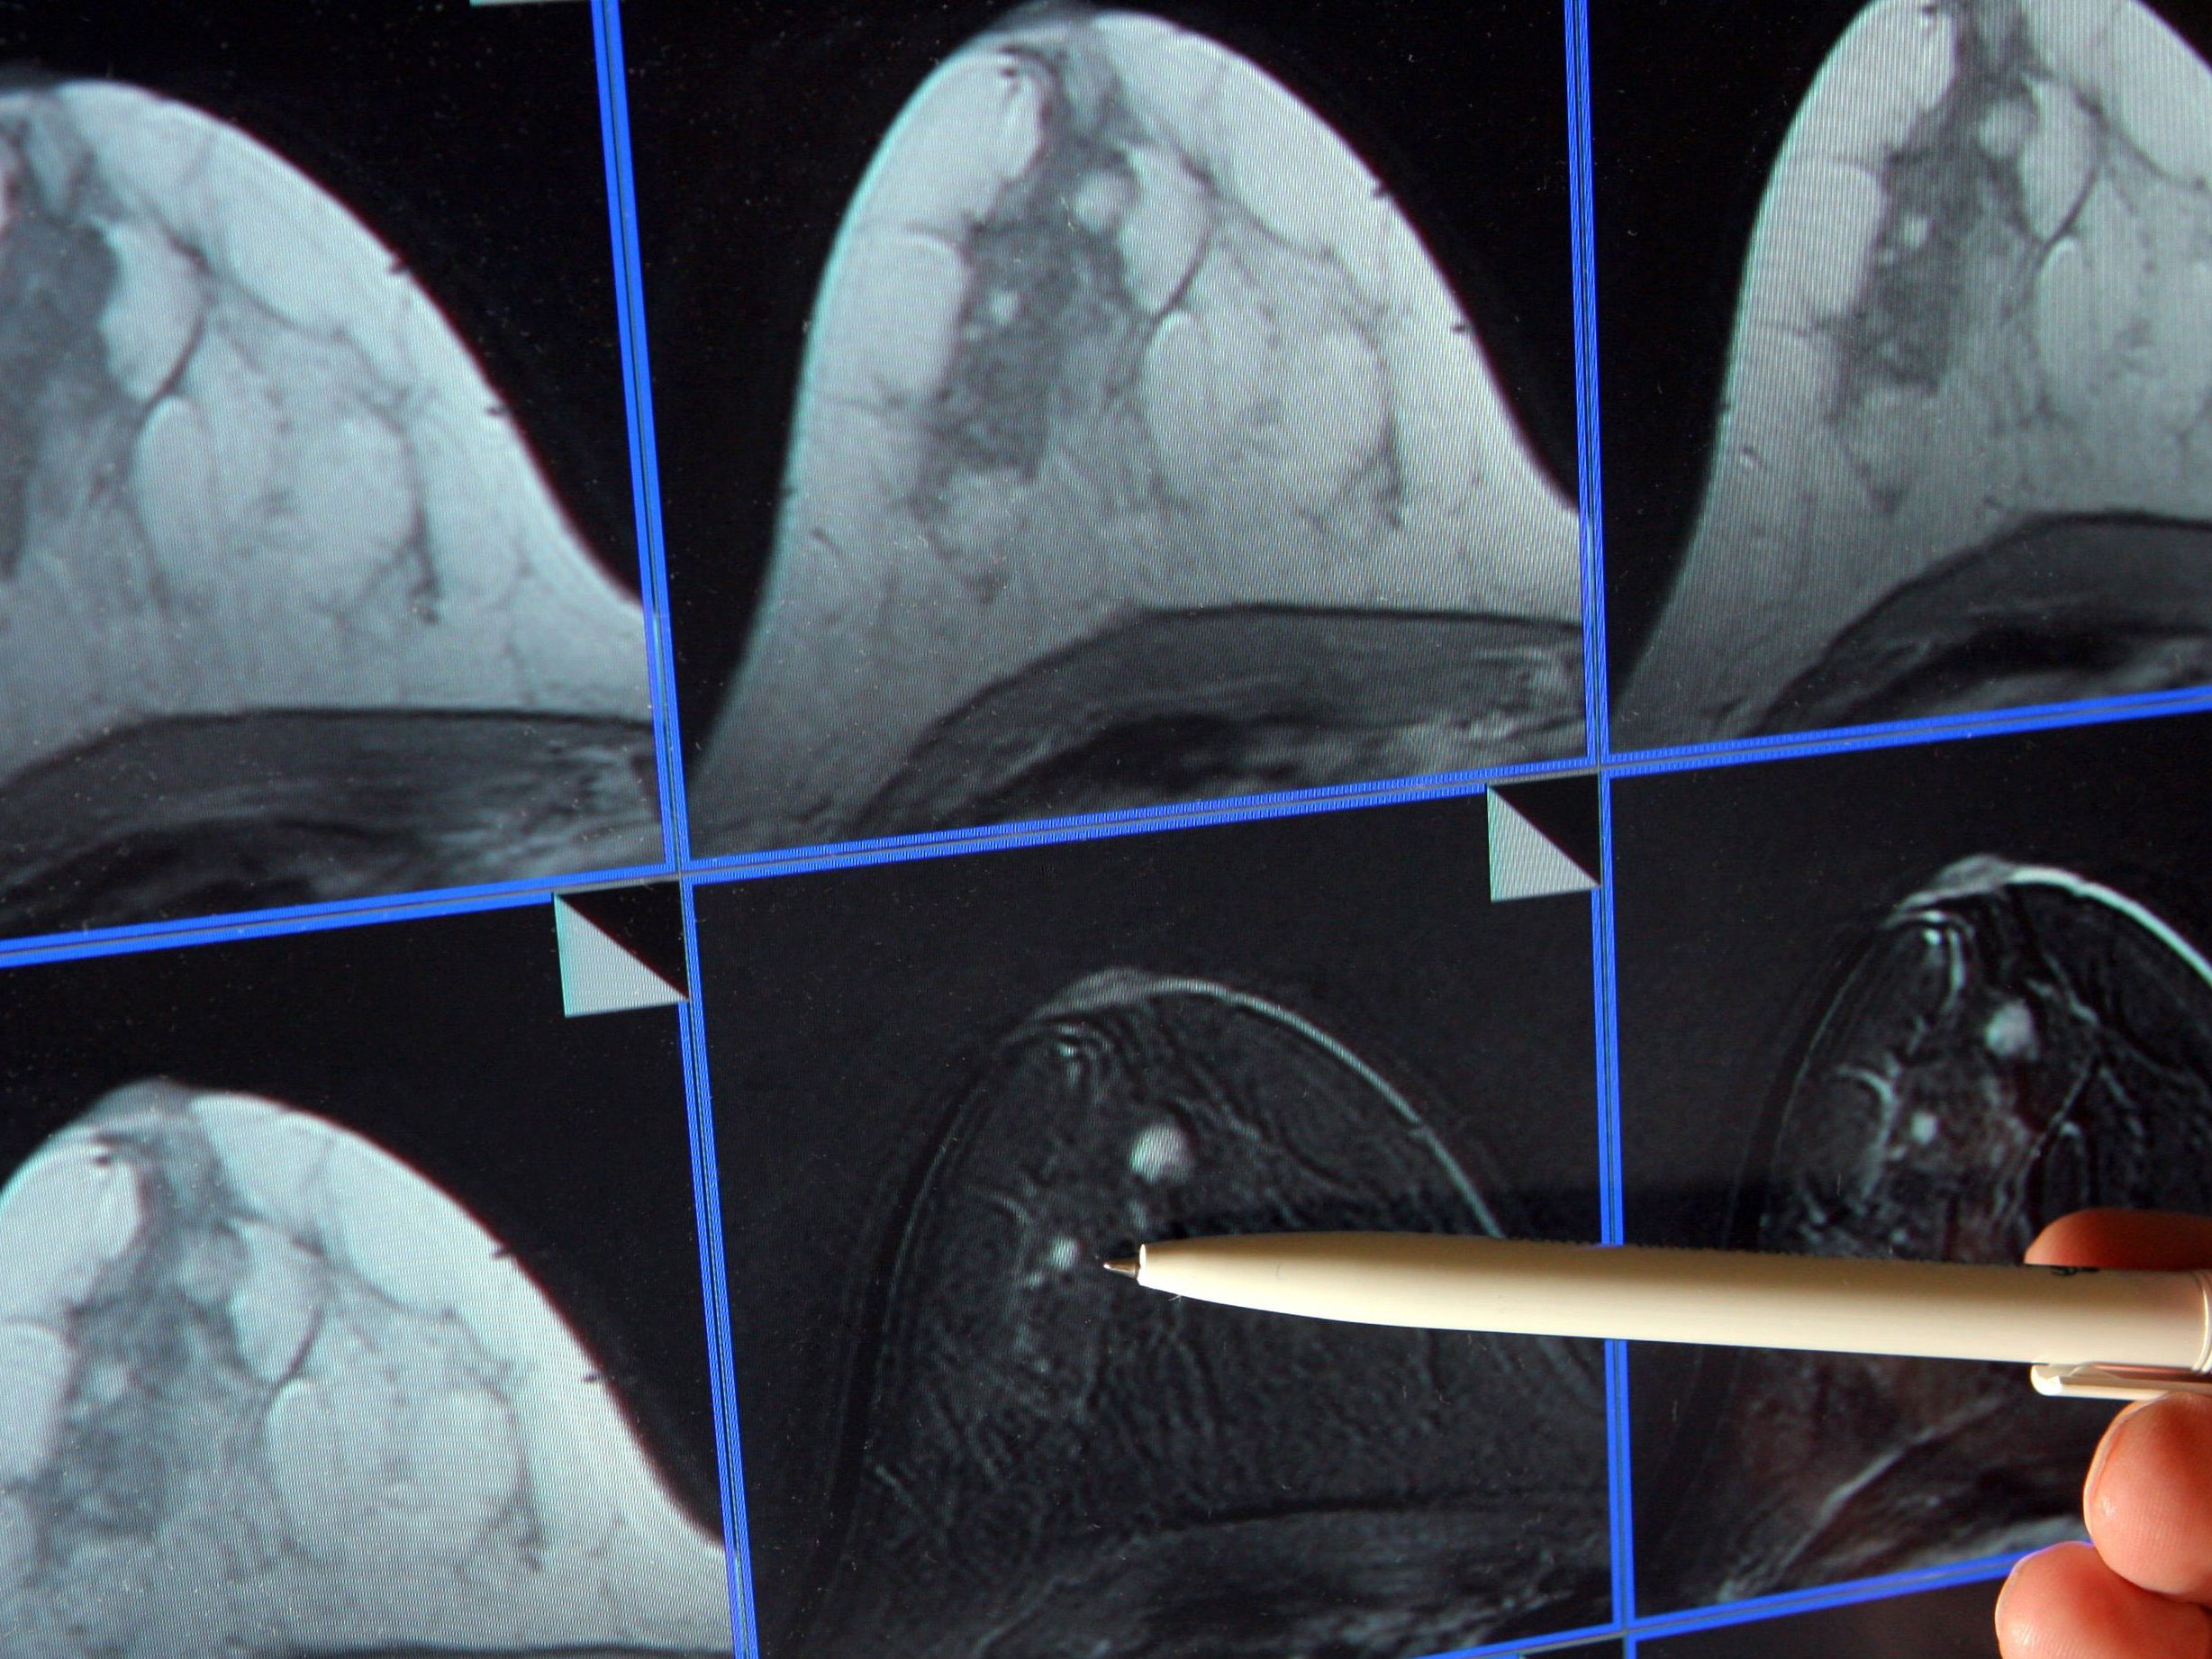

“Das ist eine Aktion der niedergelassenen Radiologen. Wichtig ist, dass Patienten mit Krebsverdacht schnell untersucht und behandelt werden. Diese Patienten können nicht warten. Wenn bei einem Patienten beispielsweise bei einer Endoskopie ein Dickdarmkarzinom festgestellt worden ist, braucht man auch möglichst bald die CT-Untersuchung”, sagte Frühwald gegenüber der APA. In Wahrheit gehe es bei den größten Problemen rund um die Kapazitäten für die bildgebende Diagnostik bei den schwerwiegenden Erkrankungen vor allem um die Computertomografie (CT), weniger um die Magnetresonanz (MR). “Die meisten onkologischen Untersuchungen werden mittels Computertomografie erbracht, wo auch der Engpass in Ostösterreich derzeit am schlimmsten ist.”

Der Vorschlag der Radiologen lautet so: Die Spitäler und die niedergelassenen Institute stellen über das bisher Geleistete hinaus zusätzliche Kapazitäten an CT-Akut-Terminen (innerhalb weniger Arbeitstage) für dringliche onkologische Untersuchungen zur Verfügung, notfalls auch außerhalb der Betriebszeiten. Bei einer Beteiligung der Wiener Spitäler wären somit mehr als 2.000 Untersuchungen pro Jahr zusätzlich für Akutdiagnostik möglich – eine Steigerung, die umgehend eine spürbare Verbesserung für die Patienten bewirken wird. Frühwald sagte: “Die Zahl von zusätzlichen 2.000 Untersuchungen würde laut unseren Berechnungen ausreichen.”